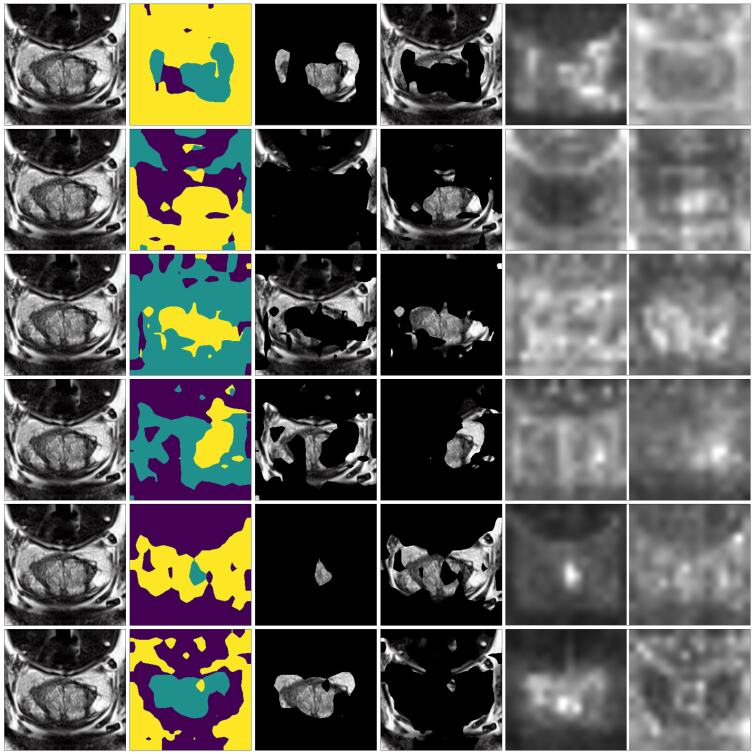

Assessing regularisation terms with cross-attention.

We assess our proposed regularisation terms on improving the accuracy of semantic correlations between prompts and concepts. We visualise the cross-attention and segmentation masks, as shown in Figure 4. Our visual results suggest that incorporating all of the proposed regularisation terms enhances concept disentanglement, whereas applying them in isolation yields suboptimal outcomes (refer to full ablation results in Appendix A.10). Moreover, the results demonstrate that MCPL-one is a more effective learning strategy than MCPL-all, highlighting the importance of excluding irrelevant prompts to maintain a focused learning objective.

Visualise concepts disentanglement and learning.

To evaluate disentanglement and prompt-to-concept correlation, we visualise attention and attention masks for learnable prompts. Figures 7 and 10 display results for both natural and medical images. The visual outcomes align with earlier quantitative findings, affirming the effectiveness of our proposed MCPL method and regularisation terms. In Figure 12 our method demonstrates capability in learning concepts having similar colour, with cross-attention derived masks outperforming pre-trained segmentation models in terms of semantic accuracy.

A.10 Full ablation results of assessing regularisation terms with cross-attention

We present in this section the full results of assessing our proposed regularisation terms in Section 3.4. The results presented in Figure 36 indicate that plain MCPL may not accurately capture semantic correlations between prompts and objects. While adding incorporating the proposed regularisation terms enhances concept disentanglement. We assess the efficacy of these terms in disentangling learned concepts by visualising attention and segmentation masks, as shown in Figure 36. Figure 37 and Figure 38 present the same visualisation of the scaled quantitative experiments involving 2 to 5 concepts.